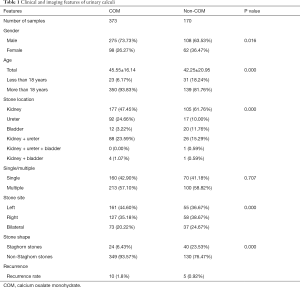

Of the 543 patients, 373 were in the COM group and 170 in the non-COM group (including 86 AUA, 28 AAU, 26 MAP, and 30 CA stones). There were 186 cases of pure calculi (142 COM, 38 AUA, and 6 AAU), and 357 cases were mixed calculi; among which, MAP and CA were all mixed. In the COM group, there were 275 men and 98 women; age 45.55±16.14 years, including 23 aged <18 years and 350 >18 years; 7 cases of recurrence after 1 year and 3 after 2 years; 1 case of combined horseshoe kidney malformation; 160 cases of single and 213 cases of multiple stones; 161 cases on the left, 127 cases on the right, and 73 bilateral cases. There were 177 cases of kidney stones, 92 ureteral stones, 12 bladder stones, 88 kidney–ureteral stones, 4 kidney–bladder stones, 24 staghorn stones, and 349 nonstaghorn stones (Table 1).